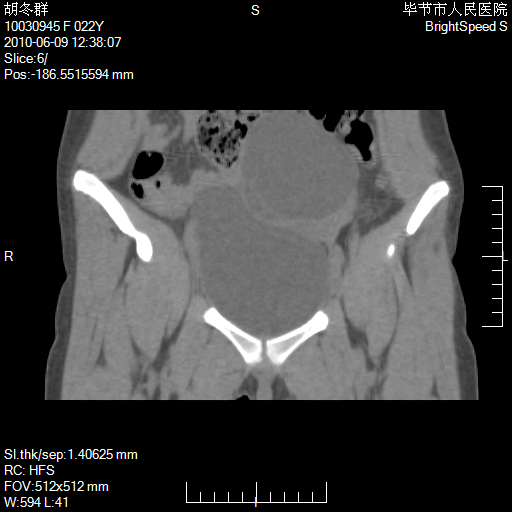

患者23岁,发现腹部包块3月。

盆腔内囊性占位;穿刺或者直接手术拿掉即可,不必紧张。

盆腔内囊性占位性病变;考虑左侧卵巢囊腺瘤。

有分隔、壁薄,支持考虑左侧卵巢囊腺瘤。

左侧卵巢浆液性囊腺瘤。

支持左侧附件区囊性占位,多考虑为囊腺瘤。

支持考虑左侧卵巢囊腺瘤;宫腔积液。

有分隔、壁薄,支持考虑左侧卵巢囊腺瘤。排尿后,膀胱缩小,由于重力作用,肿块下移就到了膀胱位置,很好理解。